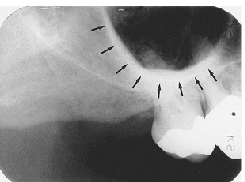

Maxillary Sinus

radiolucent area located above the apices of the premolar/molar areas in maxilla

(radiolucent)

Maxillary Tuberosity

radiopaque bulge distal to last tooth on max arch

(radiopaque)

Hamulus

radiopaque pointy projection located distal to max tuberosity

Zygomatic Arch

J or U shaped radiopaque area superior to the maxillary 1st molar region

What surrounds the maxillary sinus?

septa

What appears in the area of the maxillary canine and premolars?

inverted-y

(radiopaque, upside down y)